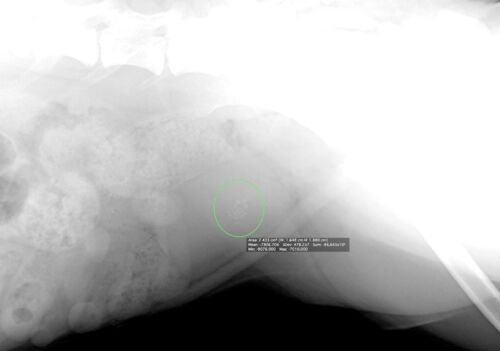

膀胱鏡を用いた膀胱結石の摘出

今回は、膀胱鏡を用いた 膀胱結石の摘出についてご紹介します。 結石に対する治療は、結石のある場所や大きさ、種類によって異なります。 内科治療としては、療法食や内服薬による結石の溶解療法、また、細菌感染による結石の形成が疑わしい場合には抗菌薬を…